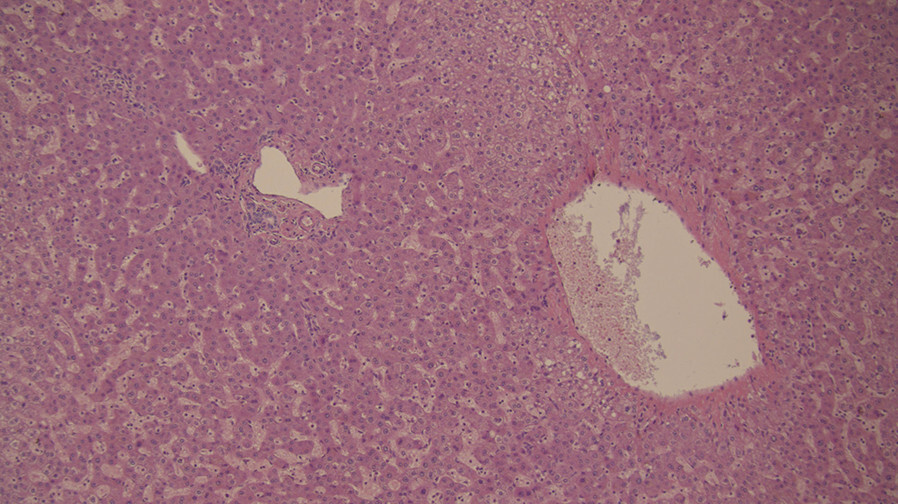

Abb. 5.25 Spektrum der MASLD.

a Normalleber, < 5% Fett.

(Quelle: Prof. Dr. B. K. Straub, Universitätsmedizin Mainz)

b MASLD, 20-fache Vergrößerung.

c MASH mit fortgeschrittener Fibrose, 20-fache Vergrößerung. (Quelle: Prof. Dr. B. K. Straub, Universitätsmedizin Mainz)

d HCC.